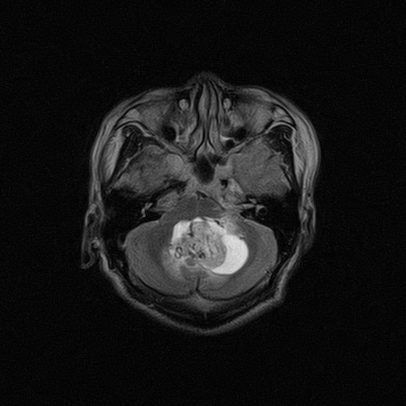

四脑室区见混杂信号占位影,脑室系统扩张明显,临近结构显著受压称位,患者52岁,多考虑室管膜瘤可能性大

定位;脑室内富血供占位

1,脑室内血管母细胞瘤。

应该是来源于小脑蚓部的占位,如血管母细瘤或星形细胞瘤

小脑血管母细胞瘤.并外压性脑积水.

小脑蚓部胶质脑膜瘤突入四脑室;肿瘤内见血管流空信号和钙化信号.

比较典型的脉络丛乳头状瘤并脑积水,鉴别小脑蚓部血管母细胞瘤。